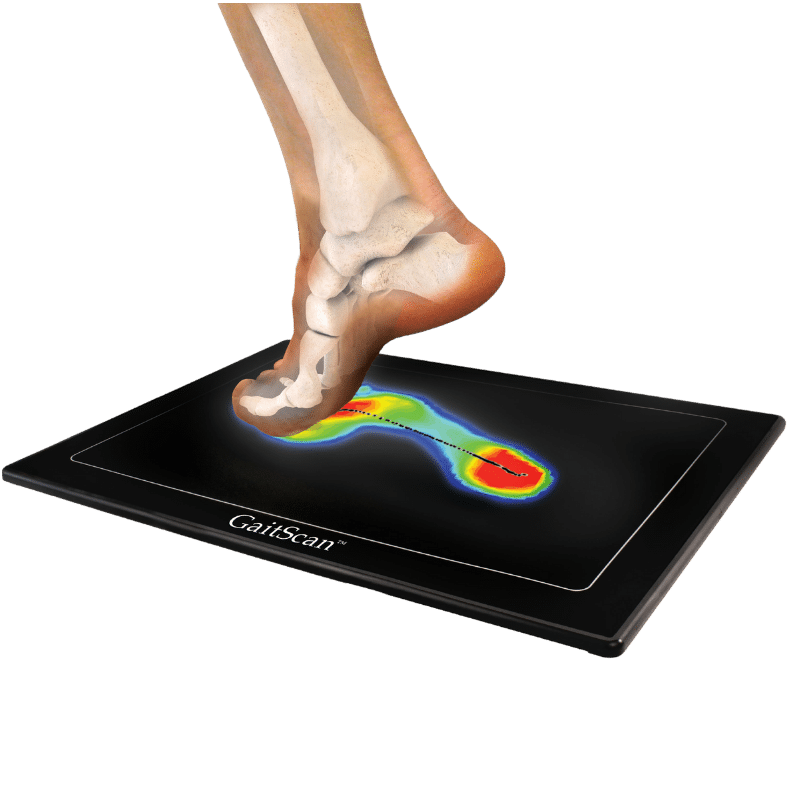

There are numerous reasons why you might need Custom Foot Orthotics. If you have pain in your foot, heel, knee or hip, have high arches or flat feet; or just being regularly on your feet and are getting any aches or pains in the feet or legs, or suffering from general foot pain while walking, running, playing sports or even at rest you qualify for Custom Foot Orthotics.